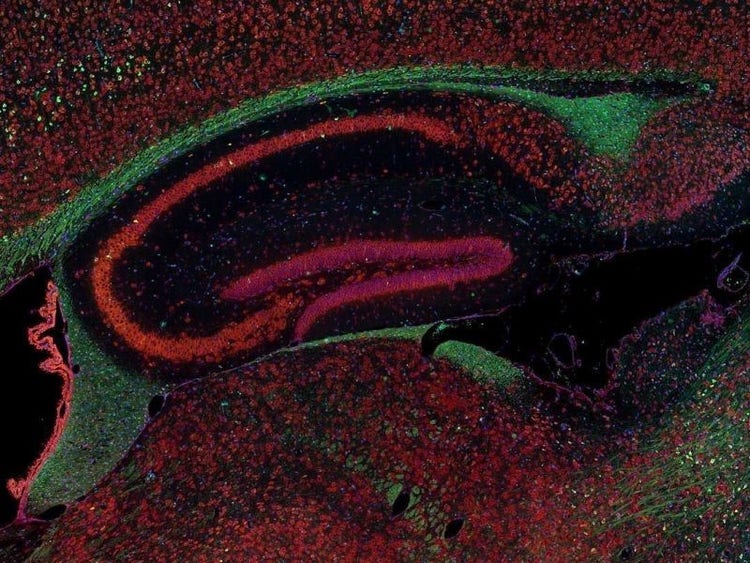

Fluorescence imaging of a mouse brain

Jedes dieser Bilder sieht aus der Nähe anders aus, aber sie fügen sich zu einem Bild eines Mäusegehirns zusammen, das mit Fluoreszenzbildgebung aufgenommen wurde.

Der britische Wissenschaftler Sir George G. Stokes beobachtete zum ersten Mal, dass das Mineral Flussspat fluoresziert, wenn es mit ultraviolettem Licht beleuchtet wird, und prägte den Begriff „Fluoreszenz“. Stokes fand heraus, dass das fluoreszierende Licht eine größere Wellenlänge hat als das Anregungslicht, ein Phänomen, das heute als Stokes-Verschiebung bekannt ist. Die Fluoreszenzmikroskopie ist eine hervorragende Methode zur Untersuchung von Materialien, die entweder in ihrer natürlichen Form (Primär- oder Autofluoreszenz) oder nach Behandlung mit fluoreszierenden Chemikalien (Sekundärfluoreszenz) fluoreszieren können.